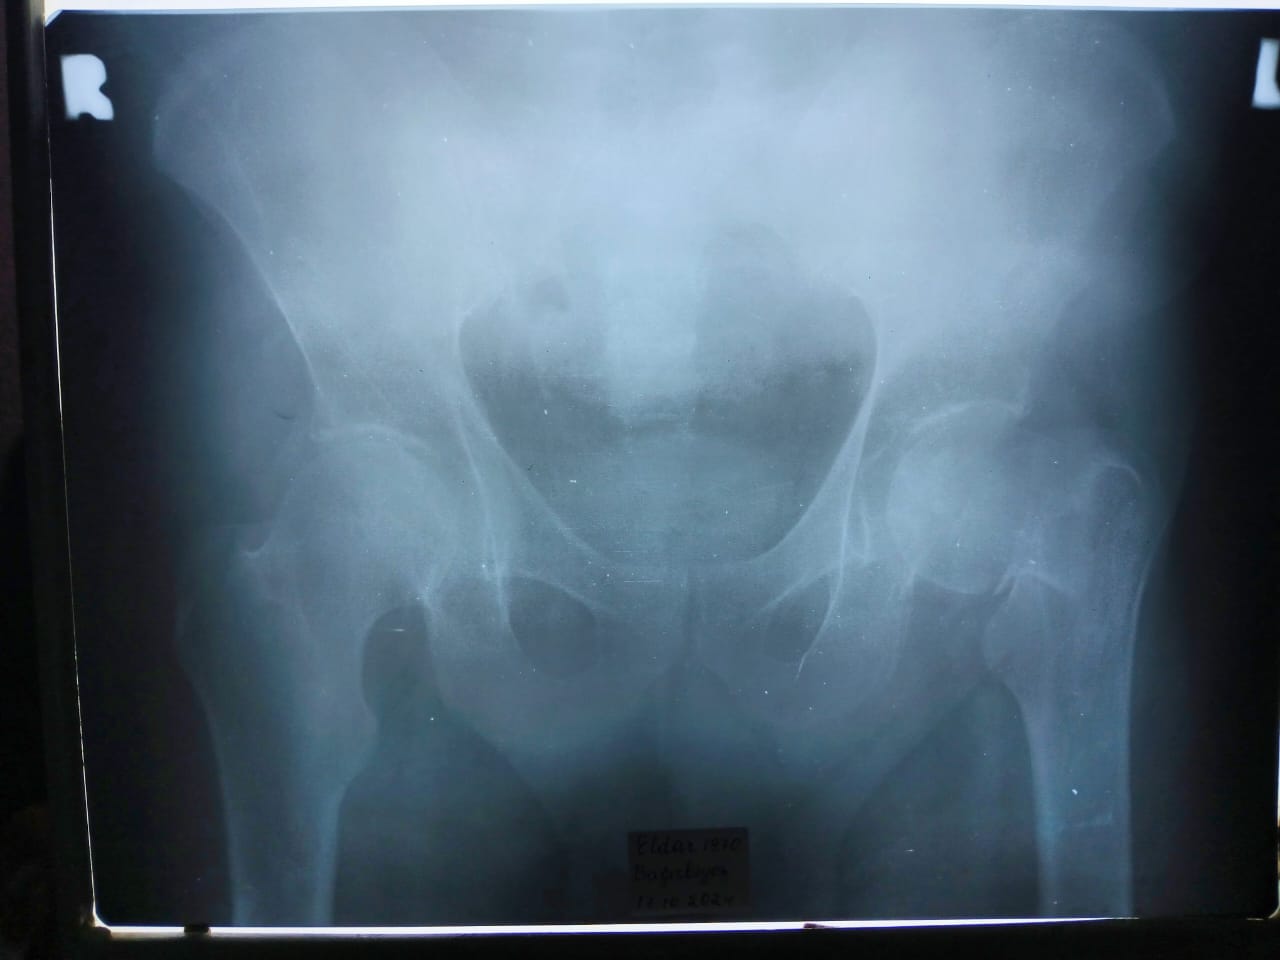

БАКУ /Trend Life/ - Популярный актер театра и кино Эльдар Багирбеков сегодня в результате несчастного случая в поселке Мухтадыр Хачмазского района упал, получив перелом шейки бедра. Об этом сообщили Trend Life в близком окружении актера.

Согласно информации, его привезли в Хачмаз, сделали рентген, а далее он будет доставлен в Баку и прооперирован под 3-4-часовым наркозом. Актеру поставят металлические спицы на 12 лет.